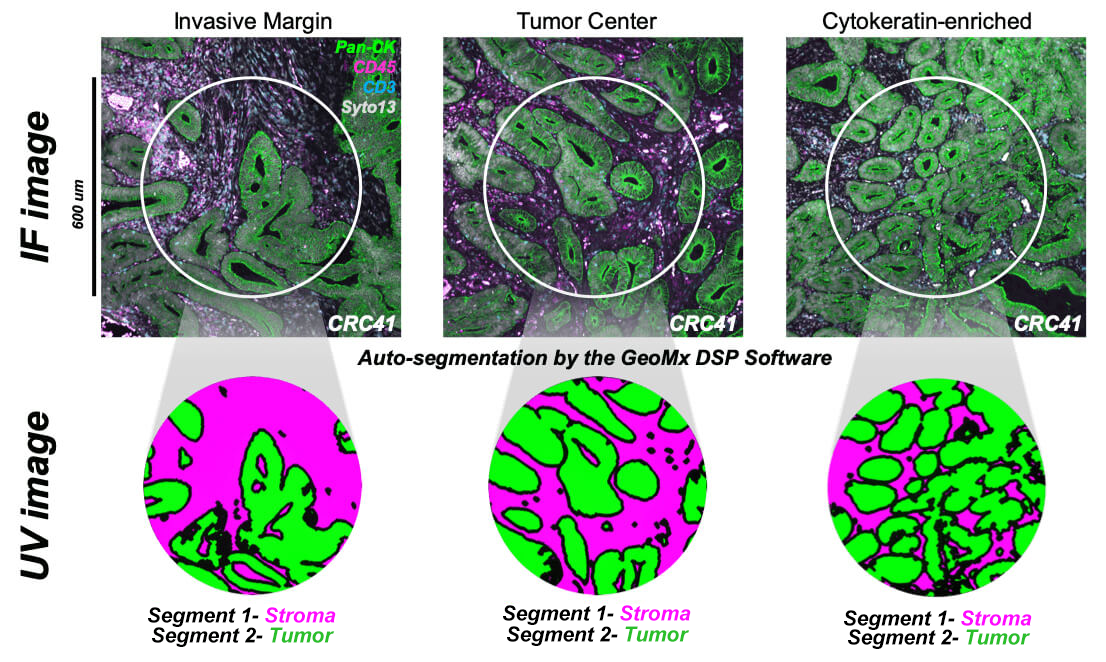

Efficiently address tissue diversity and intricate micro-environments using the GeoMx Digital Spatial Profiler (DSP), the premier spatial multiomic platform designed for both FFPE and fresh frozen tissue analysis. Unique in its field, the GeoMx facilitates non-destructive RNA and protein expression profiling from specific tissue sections and cell groups, all through an automated, scalable workflow compatible with conventional histology staining processes.

Efficiently address tissue diversity and intricate micro-environments using the GeoMx Digital Spatial Profiler (DSP), the premier spatial multiomic platform designed for both FFPE and fresh frozen tissue analysis. Unique in its field, the GeoMx facilitates non-destructive RNA and protein expression profiling from specific tissue sections and cell groups, all through an automated, scalable workflow compatible with conventional histology staining processes.